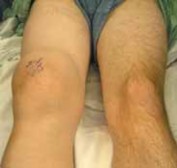

Chapter 31 Knee Arthroscopy: The Basics Steven A. Aviles and Christina R. Allen DEFINITION Knee arthroscopy…